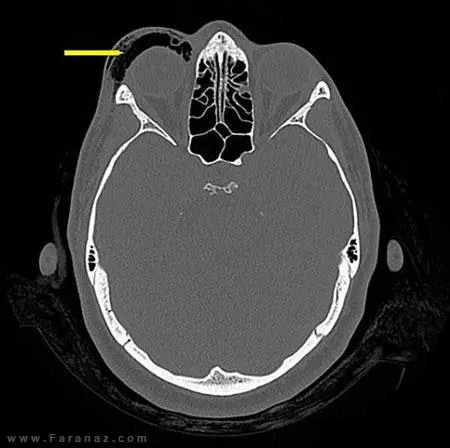

آزمایشات دقیق و عکسبرداری ها ثابت کرد که این زن دچار مشکل ” آمفزیم مداری” شده . آمفیزم مداری یعنی تورمی که در هنگام خارج شدن هوا با شدت از بینی به داخل بافت نرم اطراف چشم فشار وارد می شود بروز می کند. در موارد شدید این مشکل می تواند با وارد کردن صدمه به سیستم عصبی چشم موجب کوری شود.